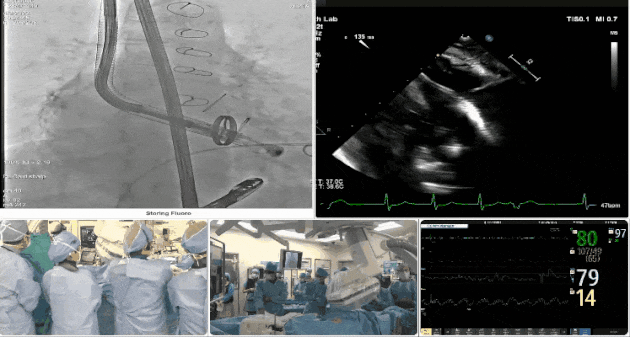

手術過程

術者采用經(jīng)右側(cè)頸靜脈入路的方式將輸送器送入患者心臟內(nèi),在TEE及DSA引導下調(diào)整輸送器頭端角度,使得輸送器與三尖瓣瓣環(huán)平面垂直。在輸送器進入右心室后釋放室間隔錨定裝置,而后釋放瓣葉夾持件(2個耳片結構)成垂直狀態(tài)。在TEE及DSA確定夾持件固定至三尖瓣葉根部且位于右室側(cè)后釋放人工瓣心房側(cè)盤片。隨后調(diào)整瓣膜同軸性以及室間隔錨定件位置(貼合室間隔),前推藏針管并固定,進而釋放室間隔錨定裝置,并再次確認瓣膜位置、穩(wěn)定性及同軸性,合攏輸送鞘后撤出輸送器,最終順利完成LuX-Valve Plus人工三尖瓣瓣膜的植入。